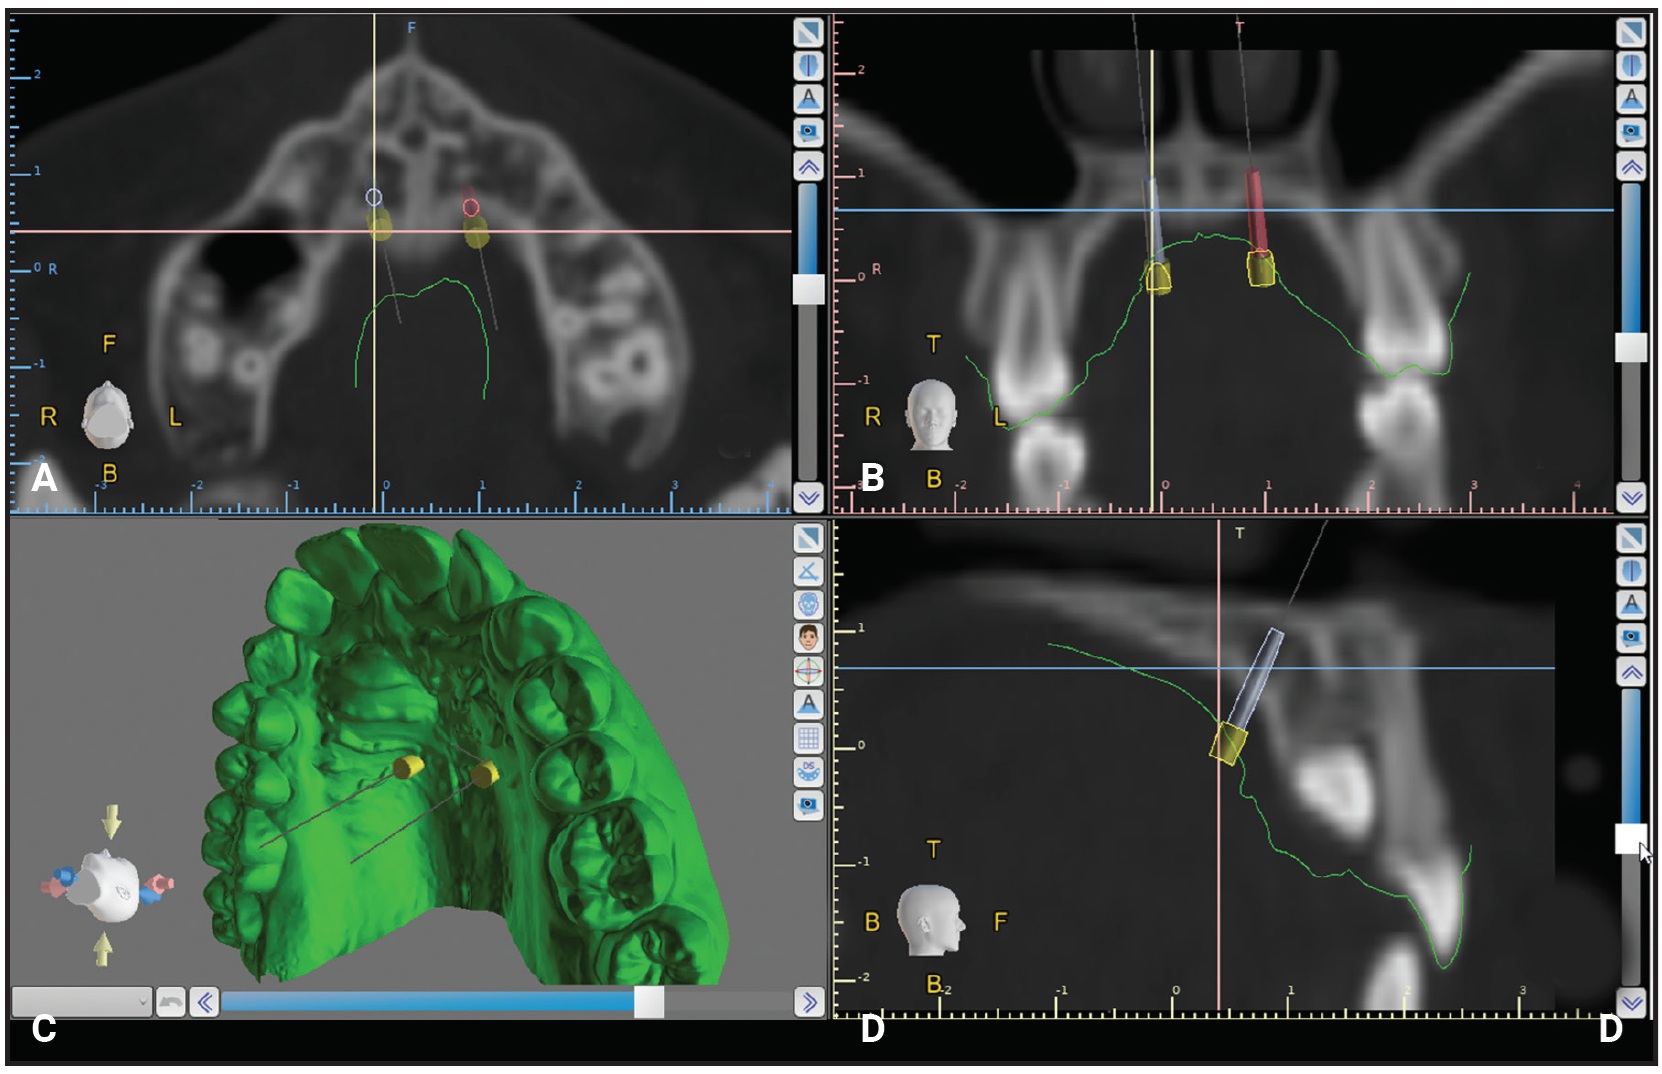

The digital miniscrews are virtually placed in the anterior region of the palate, usually at the level of the third palatal ruga.27 The clinician can adjust the position and orientation of the screws in the axial, coronal, and sagittal views as well as in the 3D rendering (Fig. 3). The objective is to ensure adequate bone support and the desired relationship with the nasal cortical bone, avoiding contact with the nasopalatine foramen—the only critical anatomical structure in terms of potential neuronal lesions during insertion. In cases of multiple miniscrew insertions, Blue Sky Plan has a feature that ensures miniscrew parallelism, facilitating insertion of the miniscrew-supported appliance. If a hybrid appliance is being designed, with bands on the maxillary molars, the miniscrew orientation should be adjusted to coordinate the screw insertion path with the band positions.

Fig. 3 Virtual planning of miniscrew insertion. A. Axial view. B. Coronal view. C. 3D rendering. D. Sagittal view.

Digital equivalents of two self-drilling miniscrews were selected with Blue Sky Plan’s “customize implant” feature. Using the coronal, sagittal, and axial views of the CBCT scans, the miniscrew orientation and insertion site were adjusted to obtain an area with adequate bone and to maintain a safe distance from the impacted canine. Adjustments were also made in the 3D view to verify proper inclination of the miniscrews in relation to the main axes of the first molars,29 as well as full coverage of the transmucosal miniscrew neck and free space between the miniscrew heads and the lateral slope of the palatal mucosa. Next, the surgical guide was digitally designed and 3D-printed*** as described above.